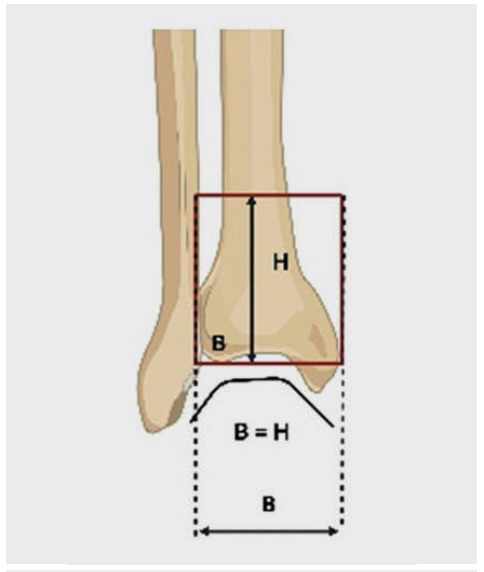

胫骨Pilon骨折是指胫骨远端干骺端骨折,累及关节面,主骨折区位于一个象限内,该象限的长度由冠状面内踝关节间隙水平处胫骨的最大宽度决定。

▲胫骨Pilon骨折是指胫骨远端干骺端骨折,累及关节面,主骨折区位于一个象限内,该象限的长度由踝关节间隙水平处胫骨的最大宽度决定。图中,B = 宽度;H = 高度。